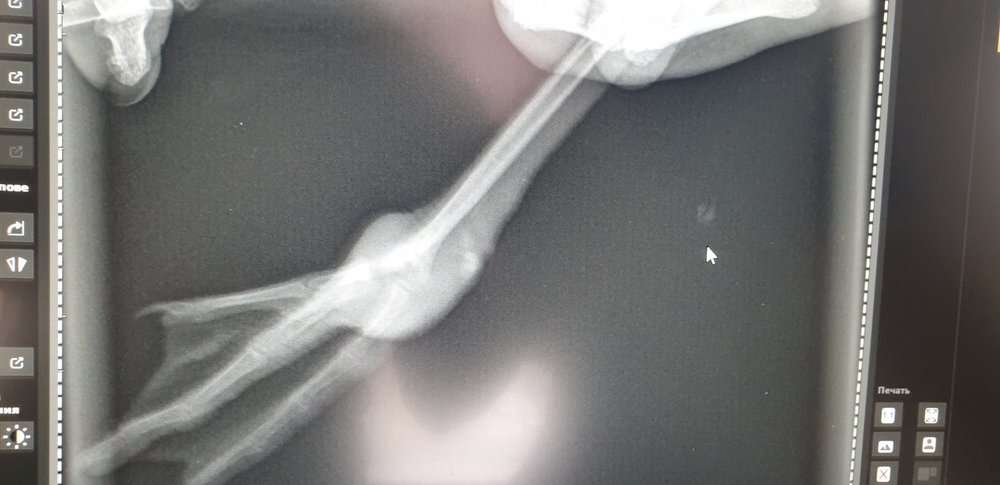

Сделали снимки. Оказалось, что у чайки два перелома. Сейчас мы каждый день перевязываем ей лапы. Чайка чувствует себя гораздо лучше, намного увереннее ходит, машет крыльями пытается взлететь. Но судя по тому, что опухоли не спадают мы не знаем, что делать дальше, она пока ещё живёт у нас на балконе.  Но скоро будут холода, чайке нужно улетать. Доктор говорит, что в таком случае её можно выпускать на волю и что лапы сами зарастут. Не хотелось, чтобы наши старания (уколы, перевязки, кормление и содержание) на протяжении нескольких недель были напрасны. Мы не знаем сколько ещё нужно её лечить, чтобы лапы зажили, а выпускать её когда на улице начнутся холода тоже не выход, чайка просто не выживет, а ей ещё нужно восстановить силы, чтобы снова вспомнить как летать.

С недолеченными лапами на воле птица будет уязвима, да и воспаление должно уйти. Когда сделан рентген? Что-то не вижу чтобы заживало. Спросите у Zosia, что делать при таких травмах.